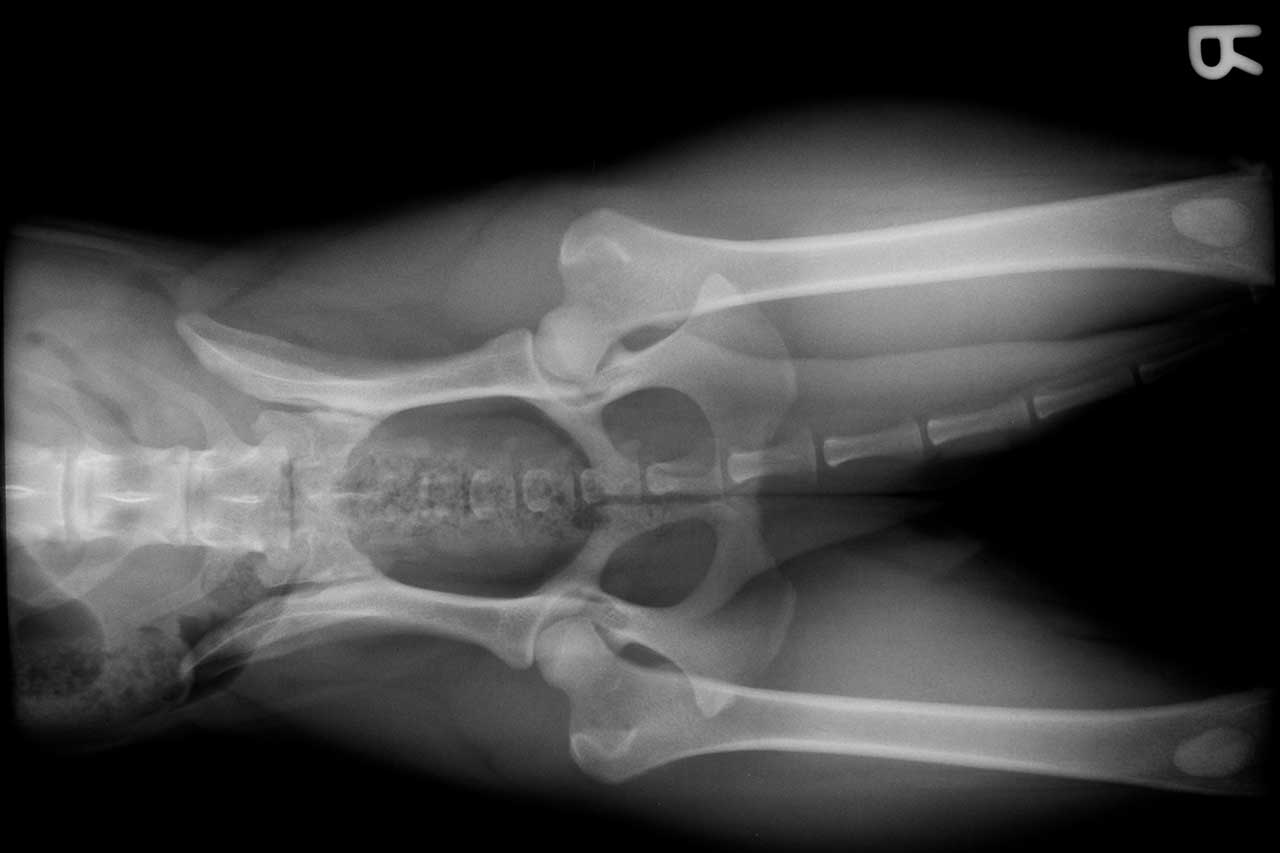

displasia de cadera

Hasta un 5% de los recién nacidos sufre displasia de cadera

Especialistas en Traumatología y Cirugía Ortopédica del Hospital Quirónsalud Sagrado Corazón alertan de que hasta un 5% de los recién nacidos sufre displasia de cadera, la anomalía esquelética más frecuente al nacimiento. Los expertos advierten que esta patología provoca una degeneración de la cadera, suponiendo, en caso de no diagnosticarse y tratarse a tiempo, una discapacidad física desde edad infantil.